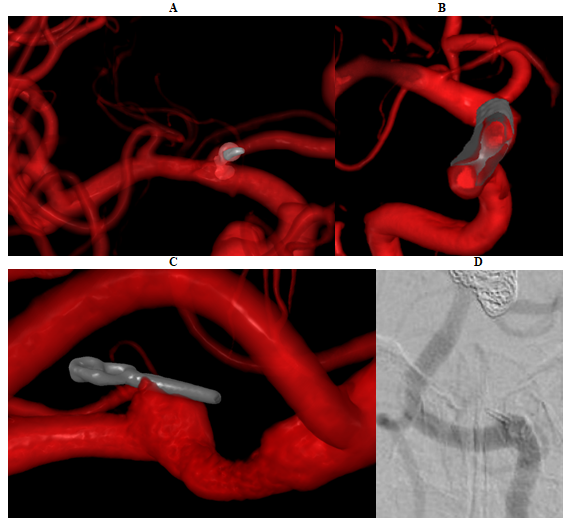

Figures 1 and 2 provided visual representation of aberrant neurovascular biomarkers in VR, which were quantified by minimal imaging important difference (Table 1) and NNI (Table 2). In NNI, CI included infinity with the exception of weighted stent stenosis in VR that had significant absolute risk reduction (11.76%, 95% CI 2.35-21.18). There were significant differences between unweighted and weighted minimal imaging important difference (test statistic t=3.70, P=0.006) and NNI (test statistic t=-2.29, P=0.05).

Figure 2 Device abnormalities detected in VR. Irregularly-shaped coil of treated posterior communicating artery aneurysm (A) protrudes into parent vessel increasing coil herniation risk. Stent-stenosis of flow diverted paraophthalmic aneurysm (B) is shown. Residual neck of clipped PICA aneurysm in VR (C) is difficult to visualize on DSA (D).